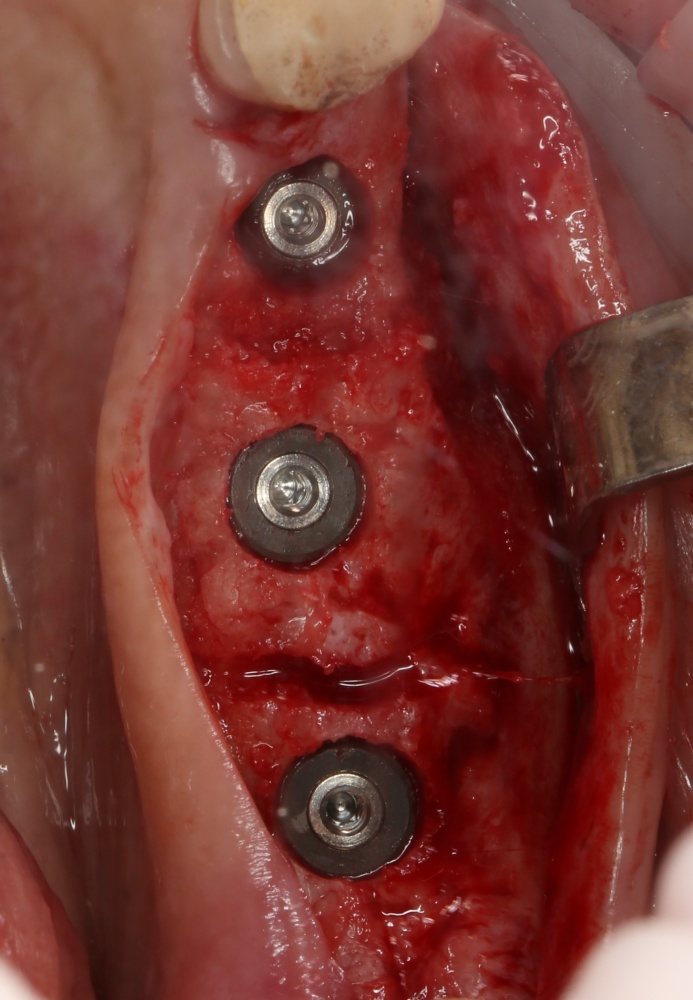

Прежде, чем приступить к аугментации (пластике) лунок зубов, мы подготовили лунки для имплантатов. В таких клинических случаях нет необходимости в использовании шаблона. Вместо этого, мы применяем общепринятые правила позиционирования и соблюдаем рекомендации производителя по хирургическому протоколу:

В процессе ирригации лунки промываются, что позволило нам еще раз подтвердить ранее сделанные выводы. С помощью аналогов имплантатов, входящих в хирургический набор Xive, мы проверили возможность стабилизации имплантатов в будущих лунках. Исходя из правил подбора и позиционирования имплантатов (я очень рекомендую почитать об этом здесь>>) мы остановились на Xive S диаметром 3,4 мм и длиной 13 мм.